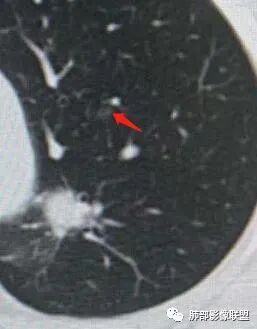

左肺上叶前段可见一磨玻璃结节,边界清,可见小叶间隔阻挡、毛刺 、胸膜牵拉,考虑微浸润腺癌。左肺上叶尖后段可见一实性结节影,边缘光整,光滑浅分叶,周围可见晕征,增强扫描明显延迟强化,可见血管贴边征,结节内未见气管及血管影,女性,考虑PSP

左肺上叶前段可见一磨玻璃结节,胸膜牵拉,考虑微浸润腺癌。左肺上叶尖后段可见一实性结节影,边缘光滑浅分叶,周围可见晕征,增强扫描明显延迟强化,可见血管贴边征,结节内未见气管及血管影,女性,考虑PSP。

一、先讨论GGN吧

1、密度?MGGN?PGGN?

2、边界?清?不清?

3、有无收缩力?有胸膜牵拉?毛刺?

4、血管连通 移动:3型?4型?

两条都进入,相互交通-4

常规判断还需要大小、CT值

大家诊断啥?

二.左肺上叶前段磨玻璃结节:

该结节较大,边界清楚,小叶间隔阻挡特征相当明显,微浸润腺癌的诊断几乎没有争议!